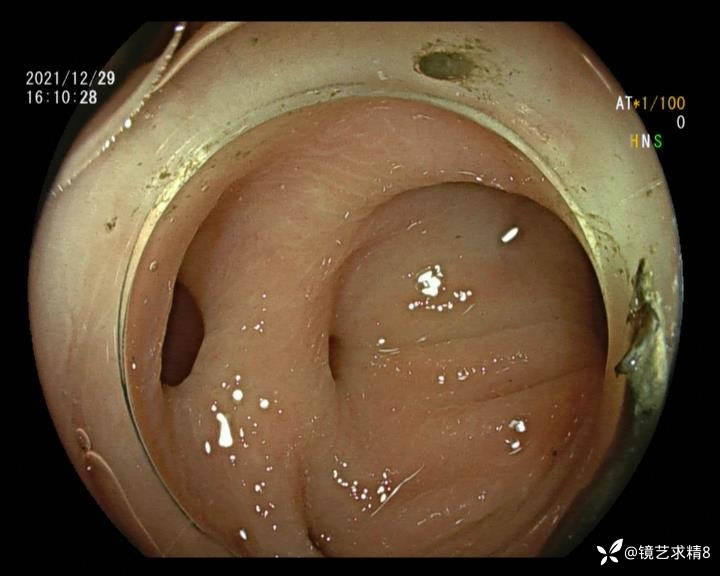

患者以消化道出血入院,胃镜未见异常,肠镜进入乙状结肠就看到很多憩室,同时还看到肠腔用清肠药后移动下来1枚尖锐的枣核,这么多憩室,这个枣核扎入憩室的机会非常大,推测应该是掉入一坑🕳就算出来还会有很多坑🕳🕳🕳等着,掉入憩室内很容易刺破血管,这可能就是消化道出血的原因,继续前进可以看到有一些憩室内翻,还有一些息肉,问题来了,那么多憩室,犯罪分子是抓住了,它在那些憩室内作过案?到达回盲部后挨个冲洗,但憩室大小又不足以把镜头进入憩室内观察,针对有血块的憩室冲洗后可疑出血的以夹子闭合或套扎,取出枣核,如果有锥形透明帽可能钻入憩室精准电凝效果更好,若内镜下操作失败介入治疗成功率更高,经内镜下治疗后观察未再出血出院。